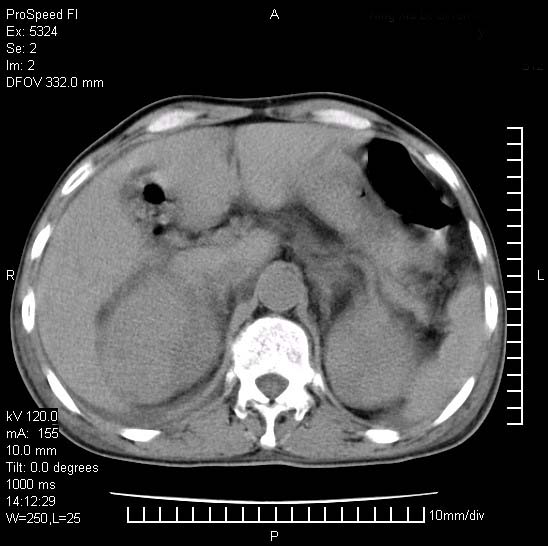

患者阴囊肿大14月,腰痛2个月,咳嗽,咳痰1周,患者现在肾功异常,做增强有些担心,我们用的是欧乃派克.

右侧肾癌伴腹膜后淋巴结转移!

右侧肾癌后腹膜转移,腹腔少量积液

腹膜后淋巴结肿大包饶腔静脉,双肾病变,建议增强

双肾均有软组织密度舯物,腹膜后淋巴结肿大包饶腔静脉------考虑为恶性占位病变,转移瘤可能。

左肾也有问题呀///

支持:双肾均见软组织密度肿块影,腹膜后淋巴结肿大包绕腔静脉------考虑为恶性占位病变,转移瘤可能。

1)考虑双肾恶性肿瘤(肾癌?)。2)腹膜后淋巴结肿大,多为肿瘤转移所致。

腹腔积液,双肾均有稍高密度肿块,主动脉旁广泛淋巴结肿大,融合,无显著肿块坏死征像,多考虑淋巴瘤累及双肾,不排除肾癌伴转移(肾癌这么大应该较多坏死了),另阴囊肿大,不知是实质肿大还是阴囊积液,如是是积液,多为腹腔肿块压近睾丸静脉所致,如是是实性的,多为淋巴瘤

1、淋巴瘤,双肾转移瘤;2、双侧肾癌,伴有腹膜后淋巴结转移。

双肾周围及腹膜后改变符合恶性病变,现在关键是要明确阴囊肿大的原因,是否为肿瘤性病变.如阴囊为恶性肿瘤那一切用转移即可解释,如阴囊为水肿改变,那需重新分析检查明确.

双肾均有软组织肿块伴腹膜后淋巴结肿大融合,右侧结肠旁沟积液;考虑恶性肿瘤。转移瘤?淋巴瘤?

阴囊肿大是实质性的么,为什么不扫阴囊,此扫描做的是什么部位,肾脏没包括全,也可以考虑生殖系统肿瘤转移

双肾增大,腹膜后多发肿大淋巴结影.首先考虑淋巴瘤.

双肾增大,结合腹膜后淋巴结肿大,考虑双肾恶性肿瘤并转移可能。

双肾癌并腹膜后淋巴结转移

考虑恶性淋巴瘤侵及双肾,腹膜后淋巴结肿大。